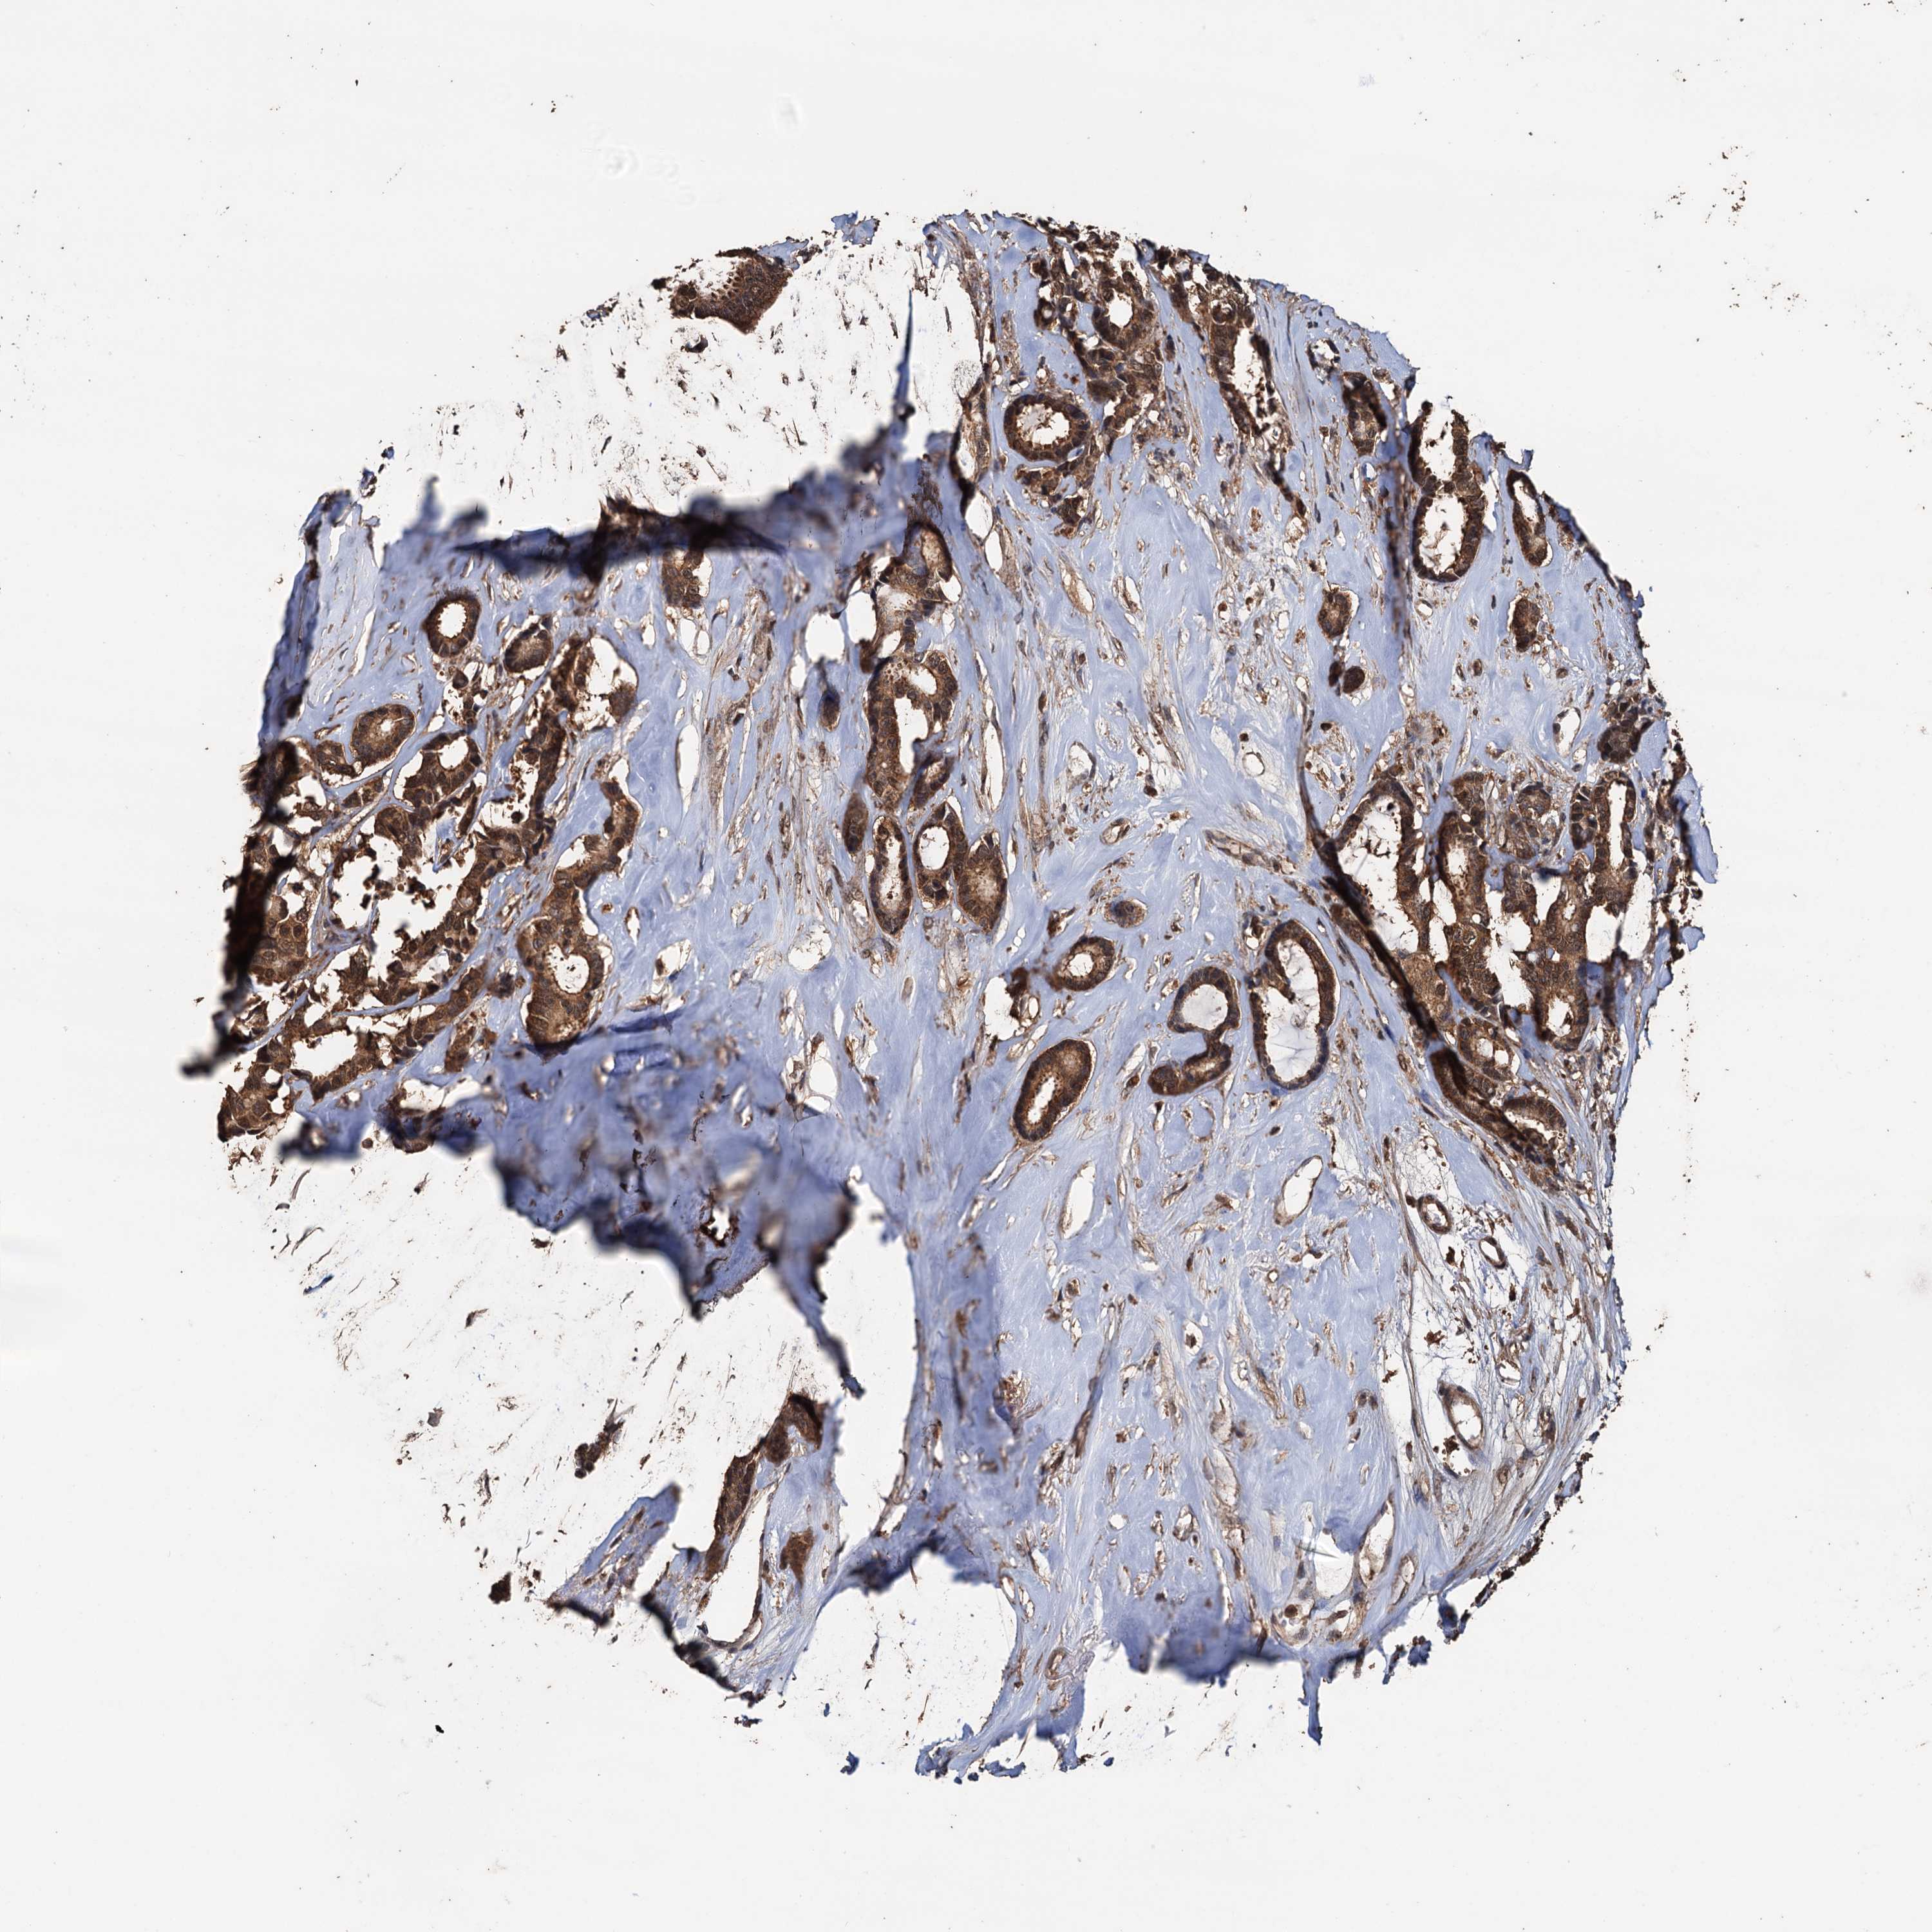

CANCER BREAST CANCER Show tissue menu

BRCA TCGA BRCA VALIDATION PROTEIN EXPRESSION